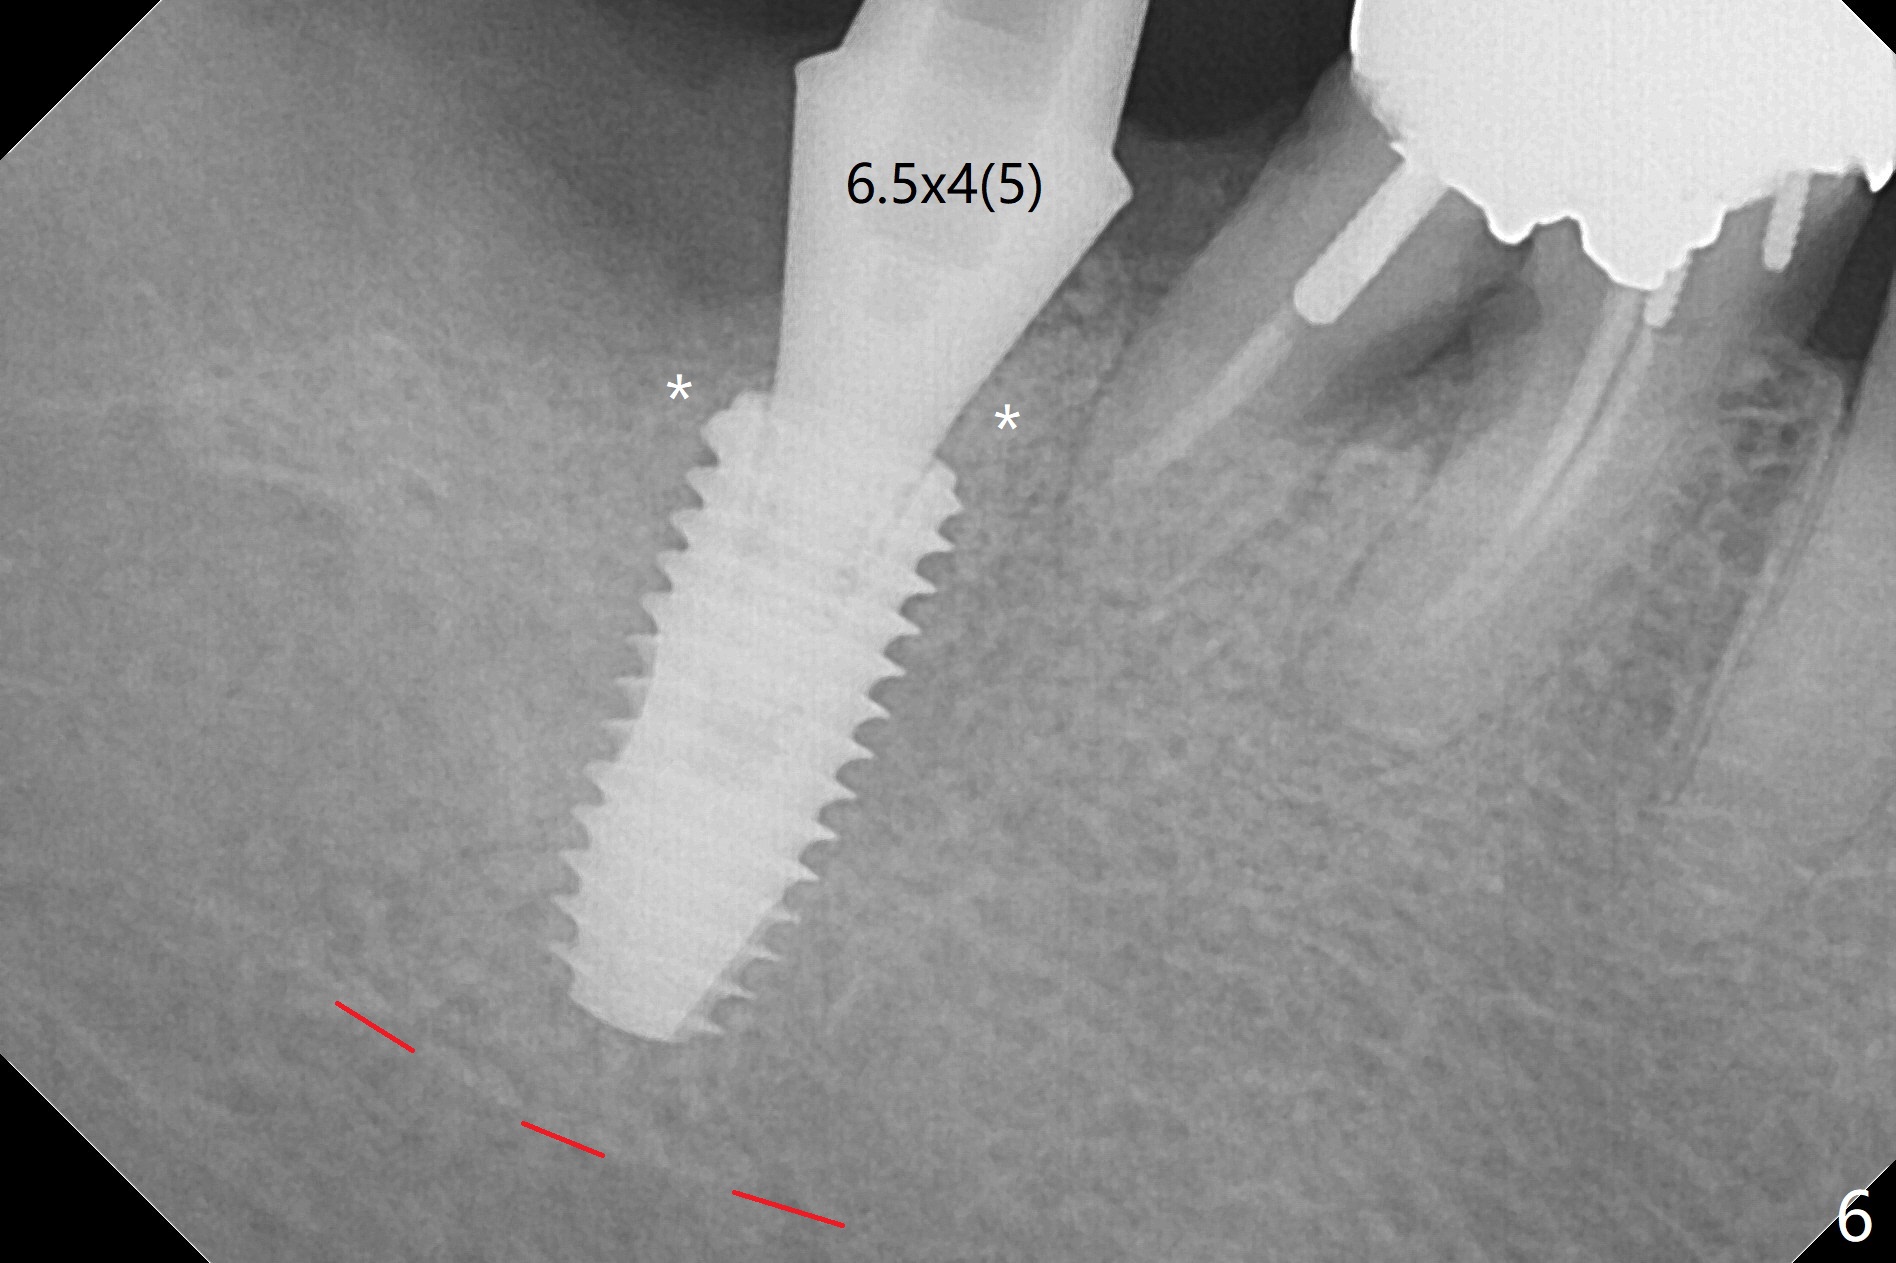

After extraction of the 2nd molar with buccal fistula (Fig.1), osteotomy is initiated beyond the socket for 4 mm (Fig.2,3). Following moving the osteotomy distal and sequential osteotomy, a 4.5x11.5 mm dummy implant is placed equicrestal buccally (Fig.4 ^) with stability; the dummy abutment is 6.5x5(4) mm. A 5x11.5 mm (definitive) implant achieves .>20 Ncm insertion torque (Fig.5). With placement of a 6.5x4(5) mm abutment, Vanilla (Fig.6 *) and Osteogen plug over the graft and in the socket of #32, periodontal dressing is applied. The implant at the 2nd molar placed much deeper than the 1st molar seems to be risky in term of the Inferior Alveolar Canal (Fig.3-6 red dashed line). Several carpules of anesthetics have to be administered in an infiltration manner for pain control. Fortunately there is no postop paresthesia. For an un-compliant patient, socket preservation is a better option. The implant seems to have osteointegrated 4 months postop (Fig.7).